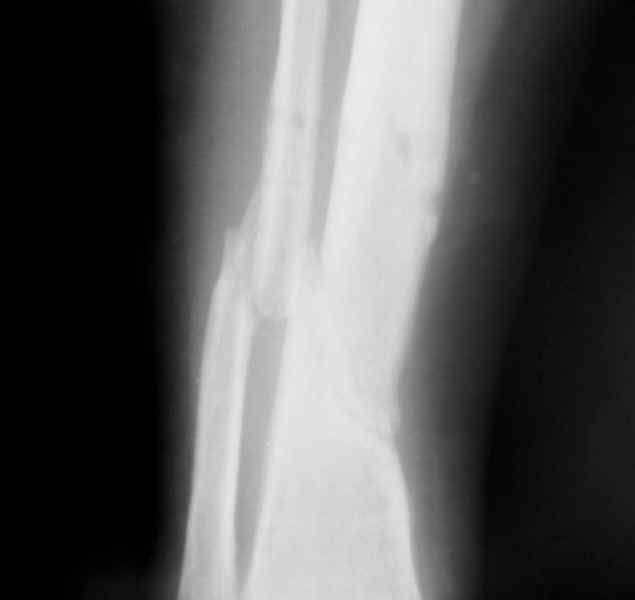

Больная 54 года, 5 м. назад открытый оскольчатый перелом 2-3 тип, Первично ЧКДО, открытое ведение раны, при этапных некрэктомия " ушел" осколок внутренней стенки б/бецовой кости, 7 сутки пластика м/тканями ,вторичные швы.

Контакт отломков только по спирали наружной стенки,заживление раны полное, на 3-4 месяце ЧКДО воздействие на регенерацию микродистрациями , 5 месяц снят аппарат по причине нестабильности и реакции м/тканей. В данный момент проблем с тканями нет, на Р-граммах псевдоартроз, клинически подвижность,больная ходит в ортезе с дозированной нагрузкой.Местно рубцовый процесс 3х5 в зоне перелома.

1. Только штифт первично динамизированныйДостаточно-ли кантакта для сращения?

2.Аддаптирующая резекция через небольшой разрез вне рубца, с оставлением костных фрагментов парадифизарно, как элемент костной пластики, штифт с динамизацией первично (возможно, на начальном этапе + 2 кольца ЧКДО с отсрочкой дистального блокирования)с последующей компенсацией укорочения транспортом на штифте.